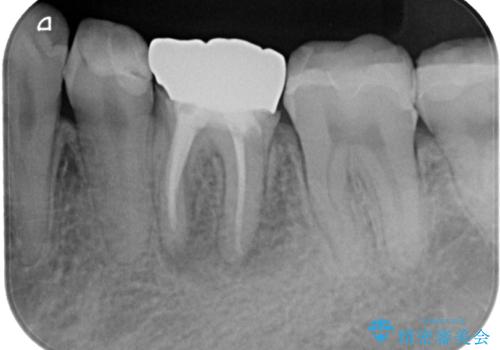

- 奥歯の歯肉から定期的に膿が出てくるとのことで来院された患者様です。

レントゲン写真などの診察を行った結果、根管治療が必要であったため、現在のクラウンを除去し、根管治療を行うこととしました。